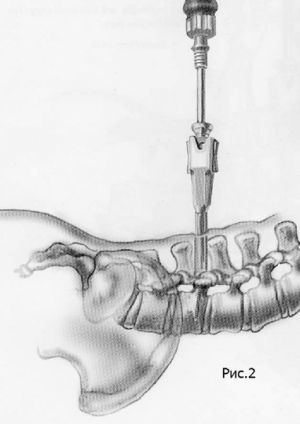

Хирургическое лечение спондилолистеза заключается в фиксации «разболтанных» позвонков титановыми винтами. Винты вводятся в позвонки через дужки позвонков (с лат. «педикули»), поэтому такая фиксация называется «транспедикулярной». Данный метод фиксации позвонков был впервые применен Roy-Camille в 1963г. и используется благодаря своей высокой эффективности по всему миру до настоящих дней.

Наиболее современным методом фиксации в настоящий момент является миниинвазивная технология введения винтов через небольшие разрезы. Этот метод позволяет меньше травмировать мышцы разгибатели позвоночника при введении винтов, а также более быстрому выздоровлению пациента и возвращению к обычному образу жизни, активному отдыху и работе. Технология данной фиксации заключается в использовании канюлированных винтов, т.е. винтов с отверстием в центре. В начале в тело позвонка вводится спица, а уже по спице вводится винт. Удаление грыжи диска и введение кейджа в межтеловой промежуток производится через тот же разрез, что и введение винтов.